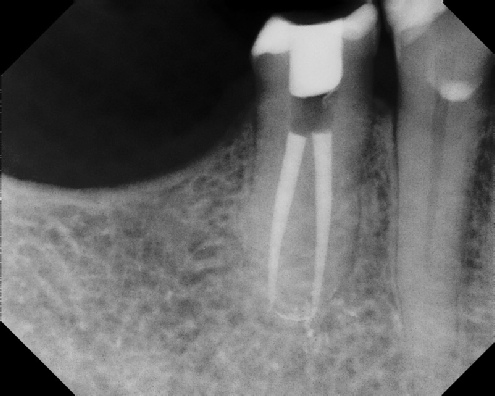

Root Canal Retreatment - Meriden 8 mos. recall Post-op Pre-op